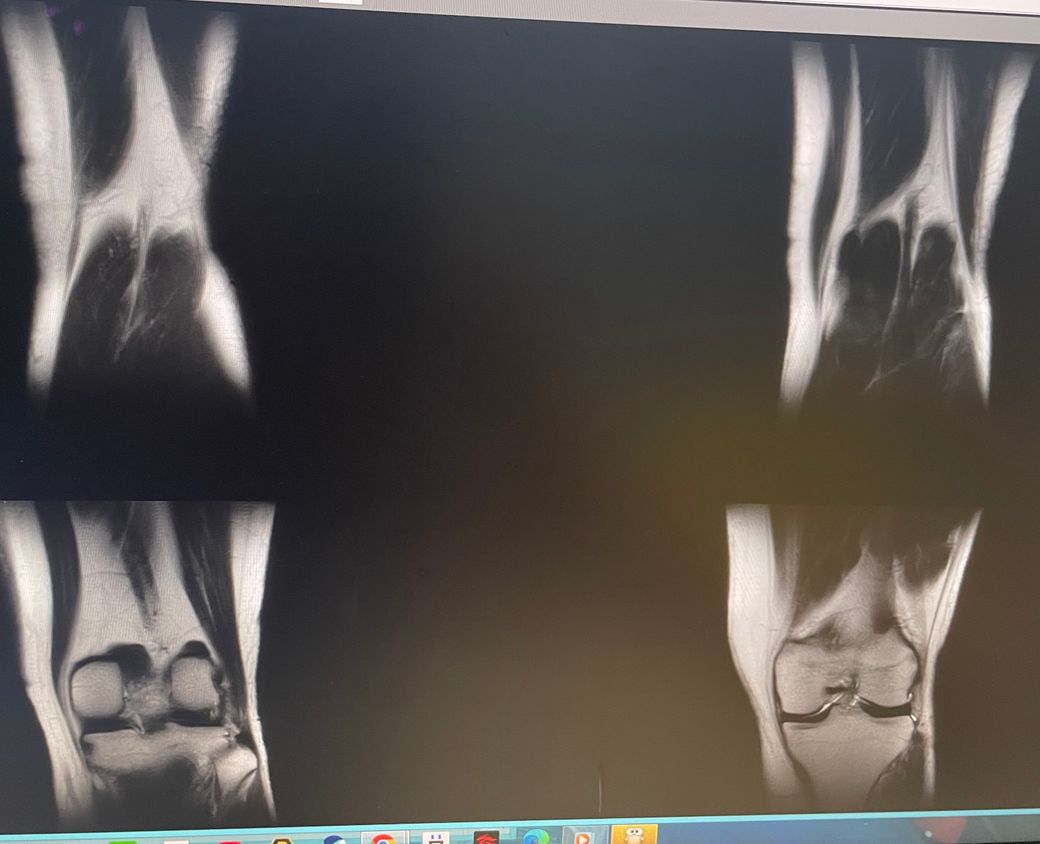

무릎 왼쪽 mri 사진 판독 부탁드리겠습니다.

현재 판독상 인대나 반월연골 손상은 없는 것으로 판독지에 기재되어 있습니다. 임상적인 증상도 중요하니 담당의사와 상의하시고 신검시에 해당과 군의관 판정을 받으시는 것이 좋겠습니다.

십자인대에는 문제가 없지만 반월판의 문제가 있는 것으로 보입니다.

ACL 즉 전방 십자 인대에 불규칙한 소견은 있으나 Tear 즉 십자 인대가 파열되었다는

소견은 관찰되지 않는 상태이며 연골에 퇴행성 변화는 있는 것으로 보이나 이 역시 R/O

으로 확실하지 않음을 의미합니다. 결과적으로 십자 인대의 파열이 명확하지 않는 상태로

군대를 연기할 사유가 될지는 모르며 전방 십자 등 인대 손상의 경우는 명확하게 파열된

소견을 보이지 않는 경우, 군 입대에 문제가 되지는 않을 것으로 생각됩니다.